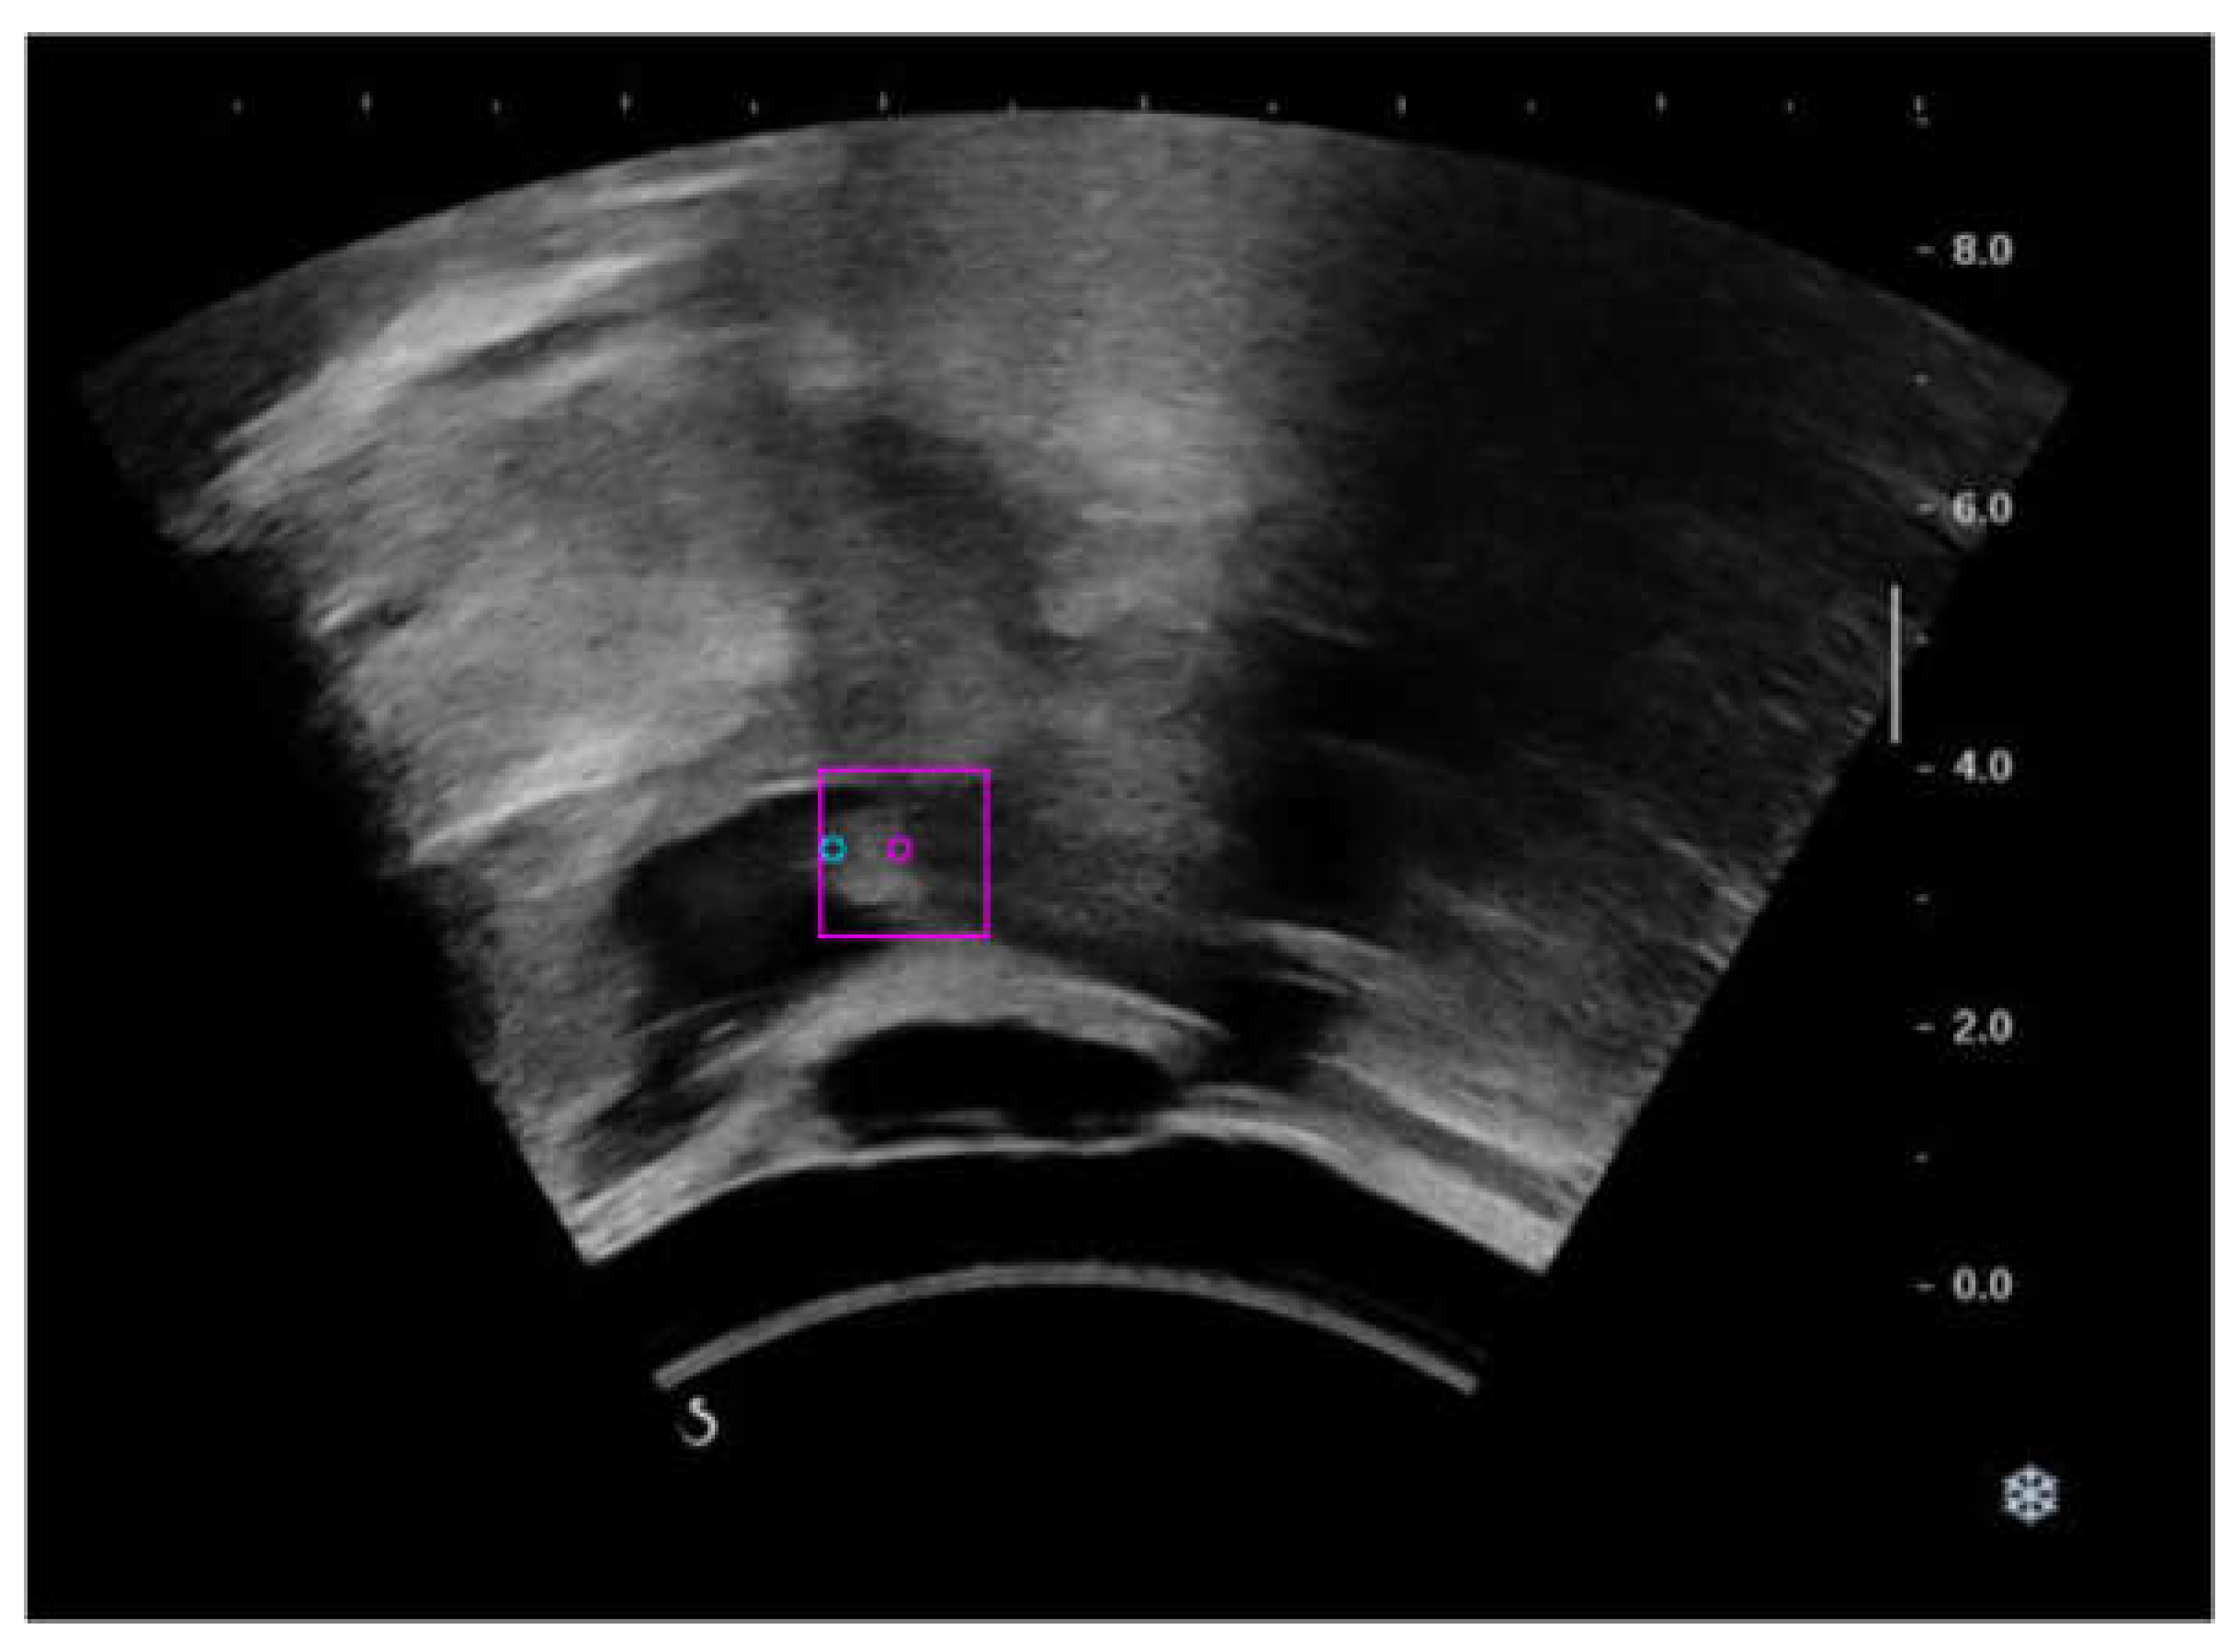

2.1. Ultrasound Swallowing Videos (USV) Dataset